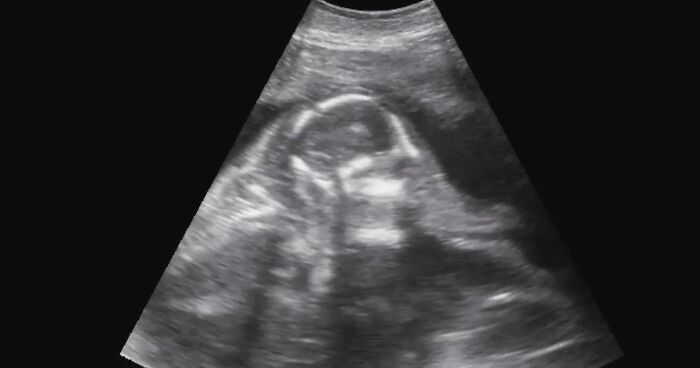

Ultrasounds are a regular procedure to check on the elephant’s pregnancy and are conducted by the zoo’s veterinary team. The most recent ultrasound—the one seen in the video—concluded that both the mother and the baby are as healthy as they can be.

Unlike with human baby ultrasounds, which are often very hard to decipher, this one is surprisingly clear. The head, the trunk, and the legs are all vivid and easy to see, but the video also points out these parts for good measure.

Pregnancies as early as 8 months are very rarely announced as there’s still another 14 months to go, but the zoo’s veterinary team feels confident as both the mom and the baby are healthy and it’s her 4th pregnancy so far, making Asha an experienced mom by now. Her diet, exercise, and training continue to stay consistent throughout the pregnancy and she’s getting the best care an elephant could have.